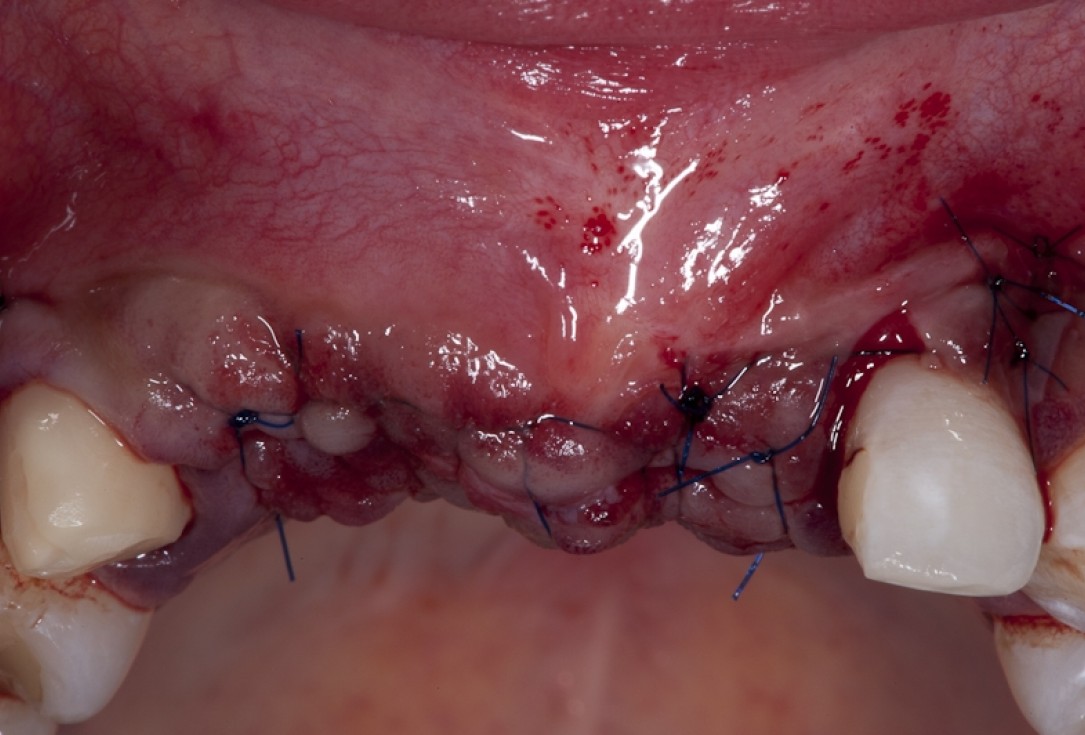

04/17 - Full flap elevation and severe hard tissue exposure